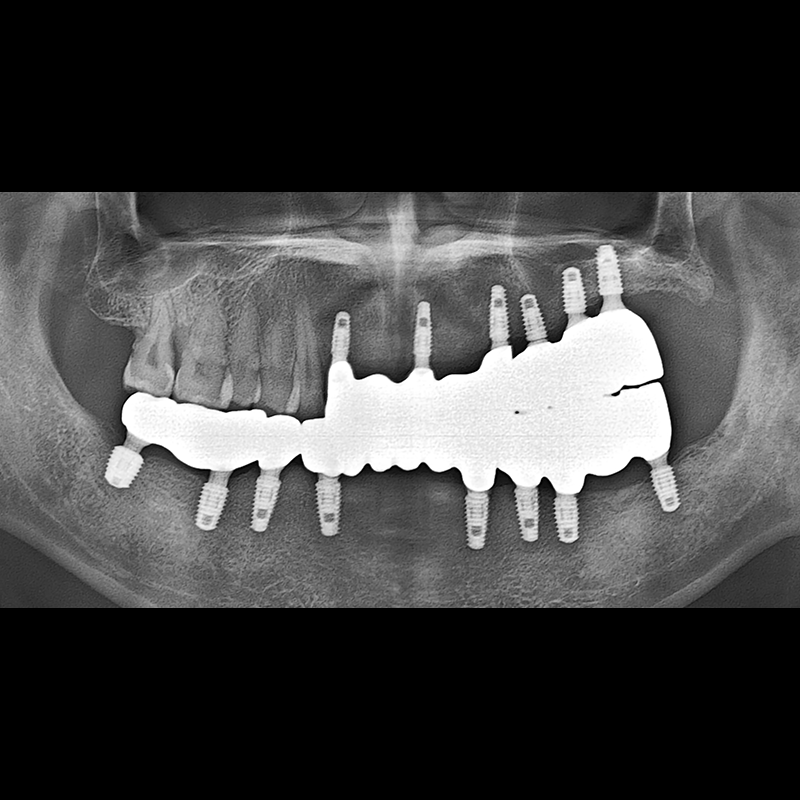

BEFORE AFTER

임플란트 전후사진 2025.05.30

결손된 치아 부분과 살리기 힘든 치아 위치에 임플란트를 식립하였습니다.